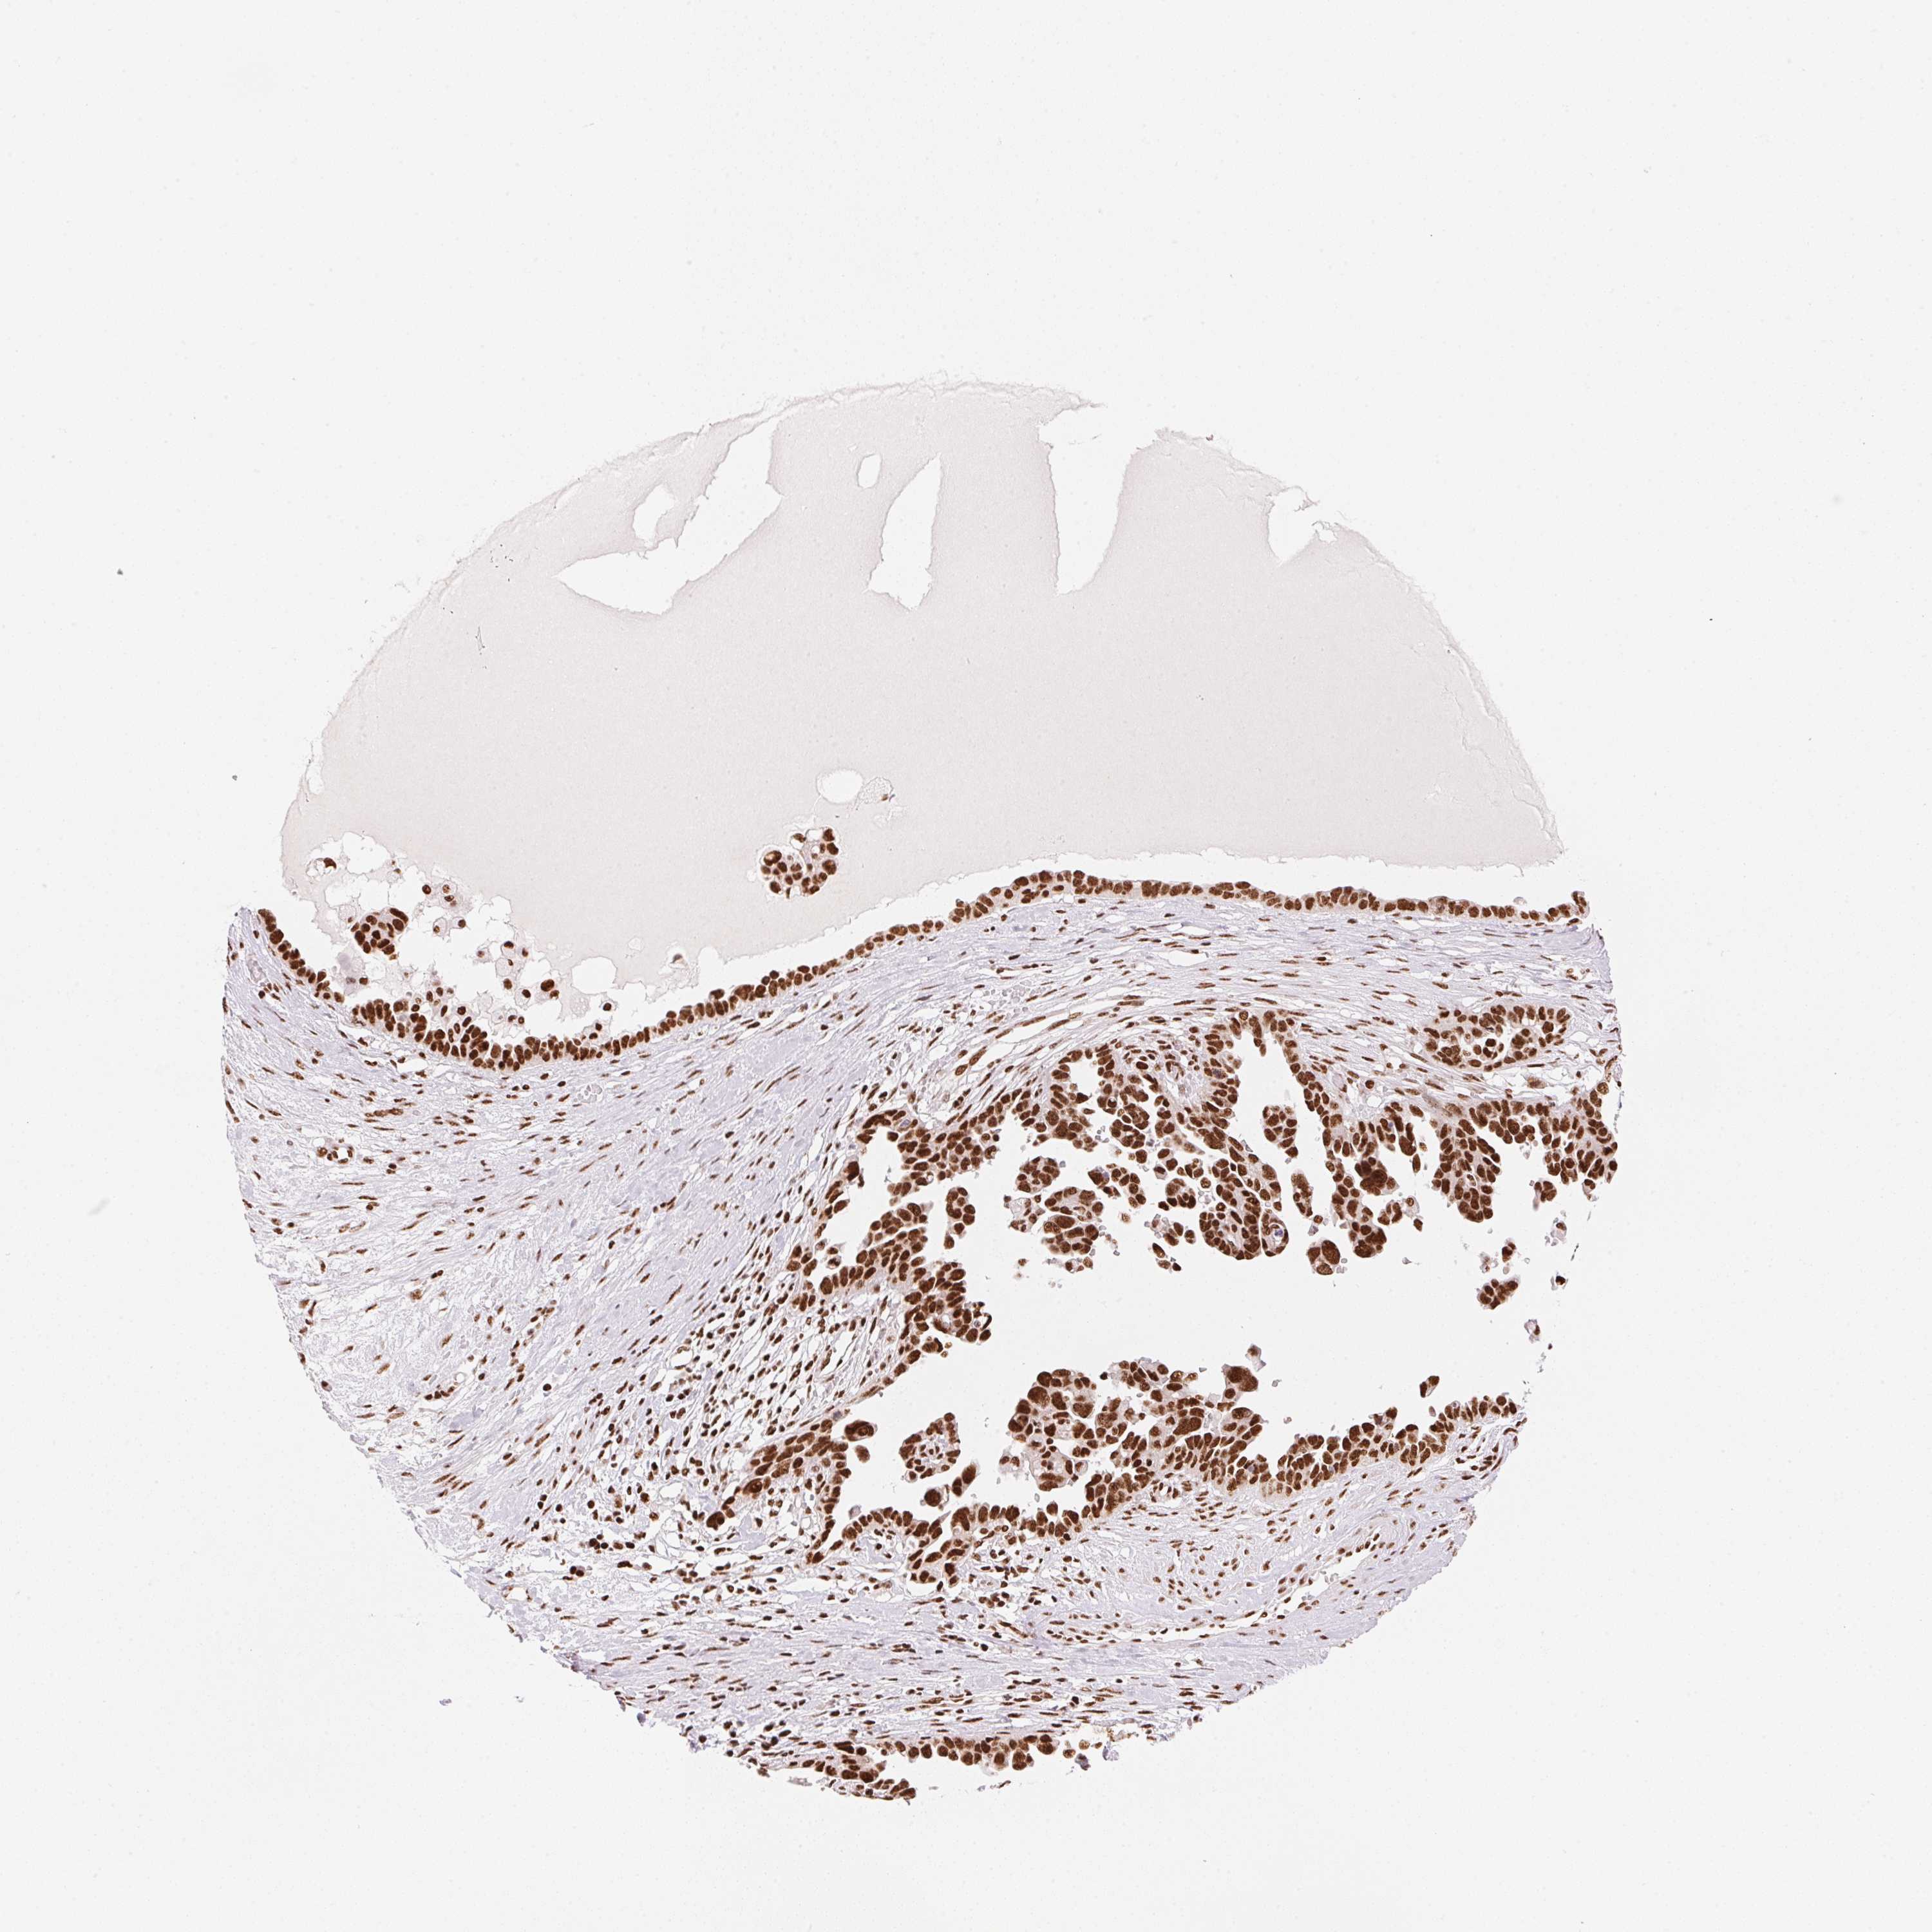

OVARIAN CANCER - Protein expressioni

A mouse-over function shows sample information and annotation data. Click on an image to view it in a full screen mode. Samples can be filtered based on level of antibody staining by selecting one or several of the following categories: high, medium, low and not detected. The assay and annotation is described here.

Note that samples used for immunohistochemistry by the Human Protein Atlas do not correspond to samples in the TCGA dataset.

Antibody stainingi

Antibody staining in the annotated cell types in the current human tissue is reported as not detected, low, medium, or high, based on conventional immunohistochemistry profiling in selected tissues. This score is based on the combination of the staining intensity and fraction of stained cells.

Each image is clickable and will lead to virtual microscopy that enables deeper exploration of all samples and also displays staining intensity scores, fraction scores and subcellular localization as well as patient and tissue information for each sample.

Antibody HPA061593

Antibody CAB016327

Staining

High

Medium

Low

Not detected

Intensity

Strong

Moderate

Weak

Negative

Quantity

>75%

75%-25%

<25%

None

Location

Nuclear

Cytoplasmic/membranous

Cytoplasmic/membranous,nuclear

Cystadenocarcinoma, serous, NOS

Cystadenocarcinoma, mucinous, NOS

Carcinoma, endometroid

Carcinoma, NOS